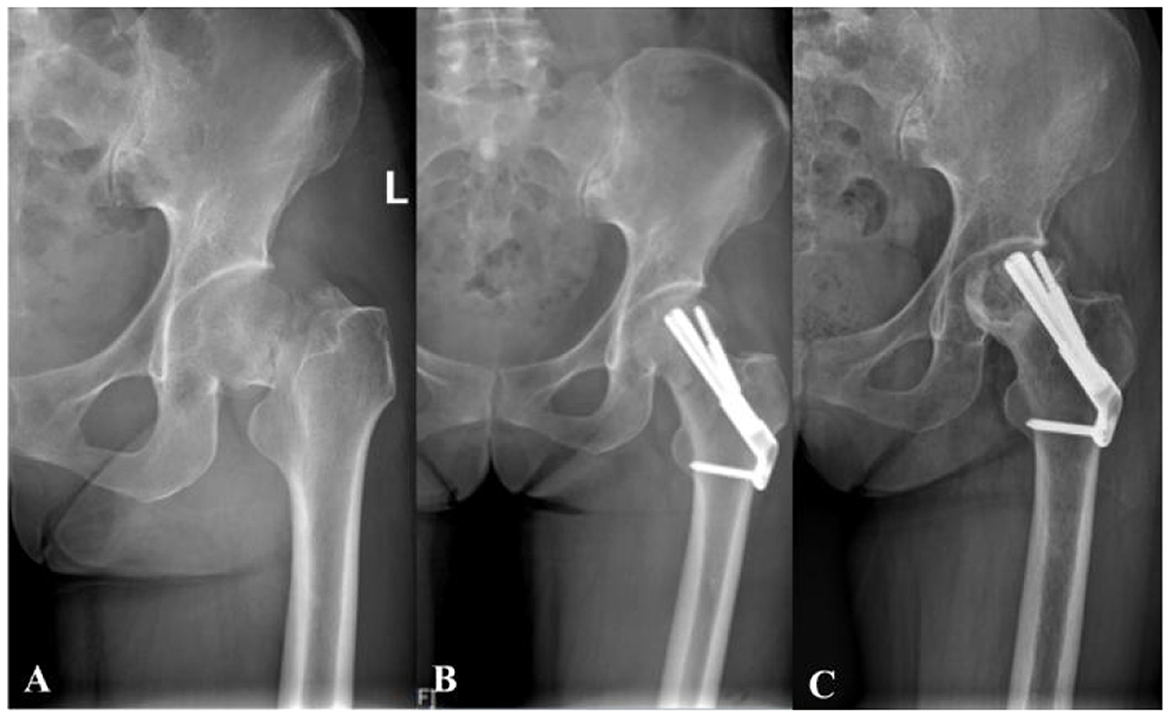

Figure 4

A 38-year-old female with femoral neck fracture. (A) Preoperative radiograph shows the initial fracture pattern. (B) Immediate postoperative radiograph demonstrates suboptimal positioning of the FNS dynamic screw in the superior region of the femoral head. (C) Final follow-up radiograph confirms the development of femoral head osteonecrosis with subsequent collapse.